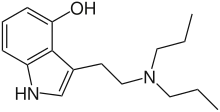

| 4-HO-DPT | artificial | 4-OH | CH2CH2CH3 | CH2CH2CH3 | 4-hydroxy-N,N-dipropyltryptamine | 63065-88-3 |